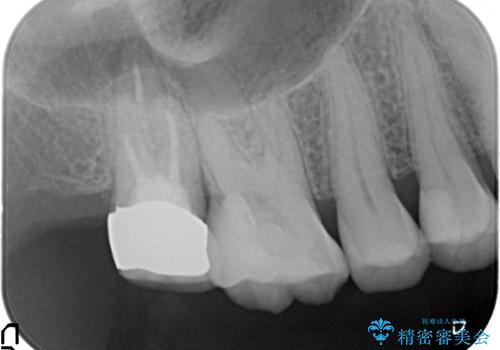

#17は失活歯で歯肉方向への縁下カリエス、#16は生活歯であるものの歯髄ギリギリの処置となるであろうとが予想される治療です。

歯周外科、マイクロスコープを用いた虫歯治療を行い歯を残す治療計画を立てます。

深い虫歯には歯周外科、マイクロスコープを用いた丁寧な虫歯の除去を行うことで歯の神経や歯そのものを残すことが可能になります。